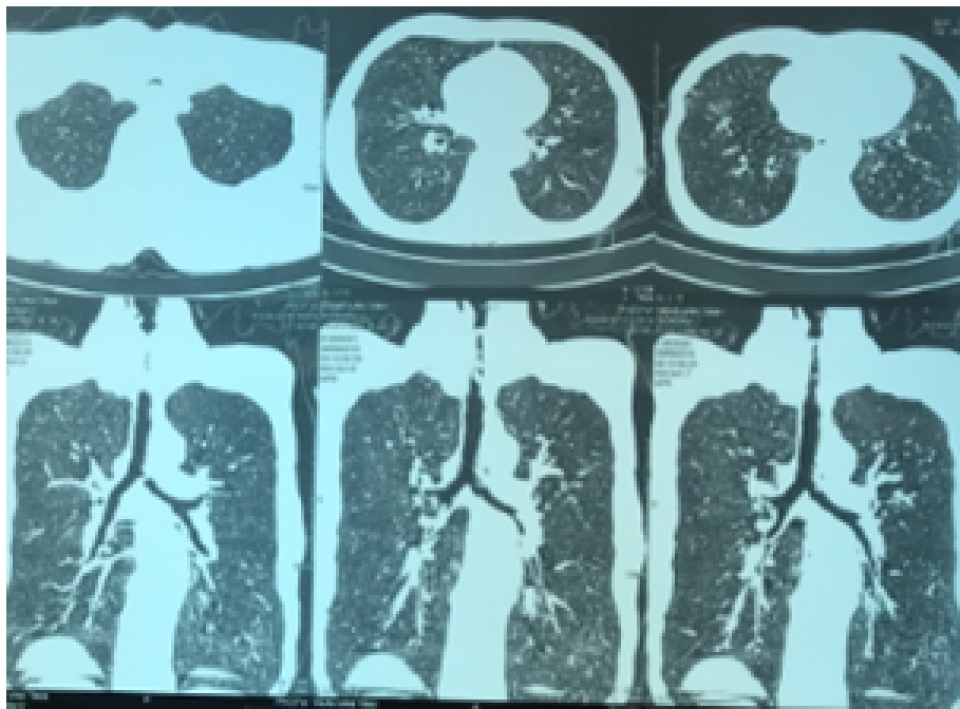

Ngày 24/9, bệnh nhân được chuyển đến Bệnh viện Phổi Trung ương trong tình trạng khó thở nhiều, có tiếng rít thanh quản. Bệnh nhân đã được chụp CT scanner ngực có hình ảnh hẹp khí quản, được nội soi phế quản cấp cứu phát hiện thấy có tình trạng xơ sẹo gây chít hẹp gần hoàn toàn khẩu kính khí quản đoạn 1/3 trên, ngay dưới thanh môn. Tình trạng hẹp khí quản mức độ nặng này có nguy cơ đe dọa tử vong ngay cho người bệnh.

| Hình ảnh chụp CT ngực bệnh nhân, có tình trạng hẹp khí quản. (Nguồn: Bệnh viện Phổi Trung ương) |